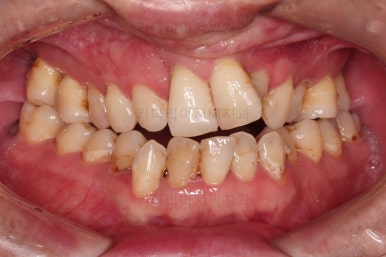

7. 전후 비교사진

치열이 정렬이 잘 되었고요.

웃을 때 보이는 치열의 느낌, 얼굴과의 조화 등 모든 부분이 좋아졌습니다.

이상 양측성 구순구개열 및 다수의 결손치아를 가진 성인 환자분의 치열교정 치료였습니다.